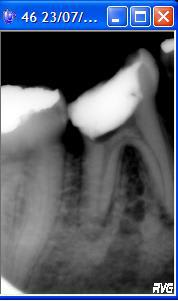

Bonjour, j'ai une patiente de 20ans que j'ai vu pour une pulpite sur 46, ouverture de chambre etc, jusque là classique.

Le problème c'est la radio (cf pièce jointe). Je pense à un pulpolithe (à seulement 20ans :s) mais je ne sais pas quoi en faire...

Si j'essaye de le faire sauter vu l'épaisseur du plancher et l'existence probable des multiples canaux accessoire pour faire une couronne sur cette dent ca va être périlleux.

Si je le laisse je crains les douleurs et une contamination de mon endo...

J'ai aussi une image bizarre au niveau des racines mésial (début de résorption?), je referrais une radio.

vu la longueur de la racine distale, la carie qui descend très bas, un IC + CCM n'ira pas loin dans le temps

je pose une question peut etre idiote mais vu la taille de la dent, il ne pourrait pas s'agir de sa molaire de lait, pas de résorption, suite à une agénésie de sa permanente?

Il faut confirmer qu'il s'agit bien d'une calcification et que le plancher se situe bien juste au dessus de la furcation. Pour cela, tu peux voir la dent controlatérale.

Tu es sûre qu'il s'agit d'une véritable 46 ?? ça ressemble à une dent de lait non ????

Mouais, je penche pour une dent lactéale également. La chambre d'une 46 ressemble pas à ça, là elle est trop large, les canaux trop rectilignes.

Pour le "plancher" que je vois pour le moment c'est jaunatre et granuleux, pas lisse, j'ai jamais vu un tel aspect (jamais vu de pulpolithe non plus).

Sinon je n'ai pas vu la patiente ce matin, elle n'est pas venue.. mais effectivement je m'étais fait la réflexion que les racines étaient plus courtes mais l'hypothèse "dent de lait" n'a pas fait son chemin (un peu honte quand même).